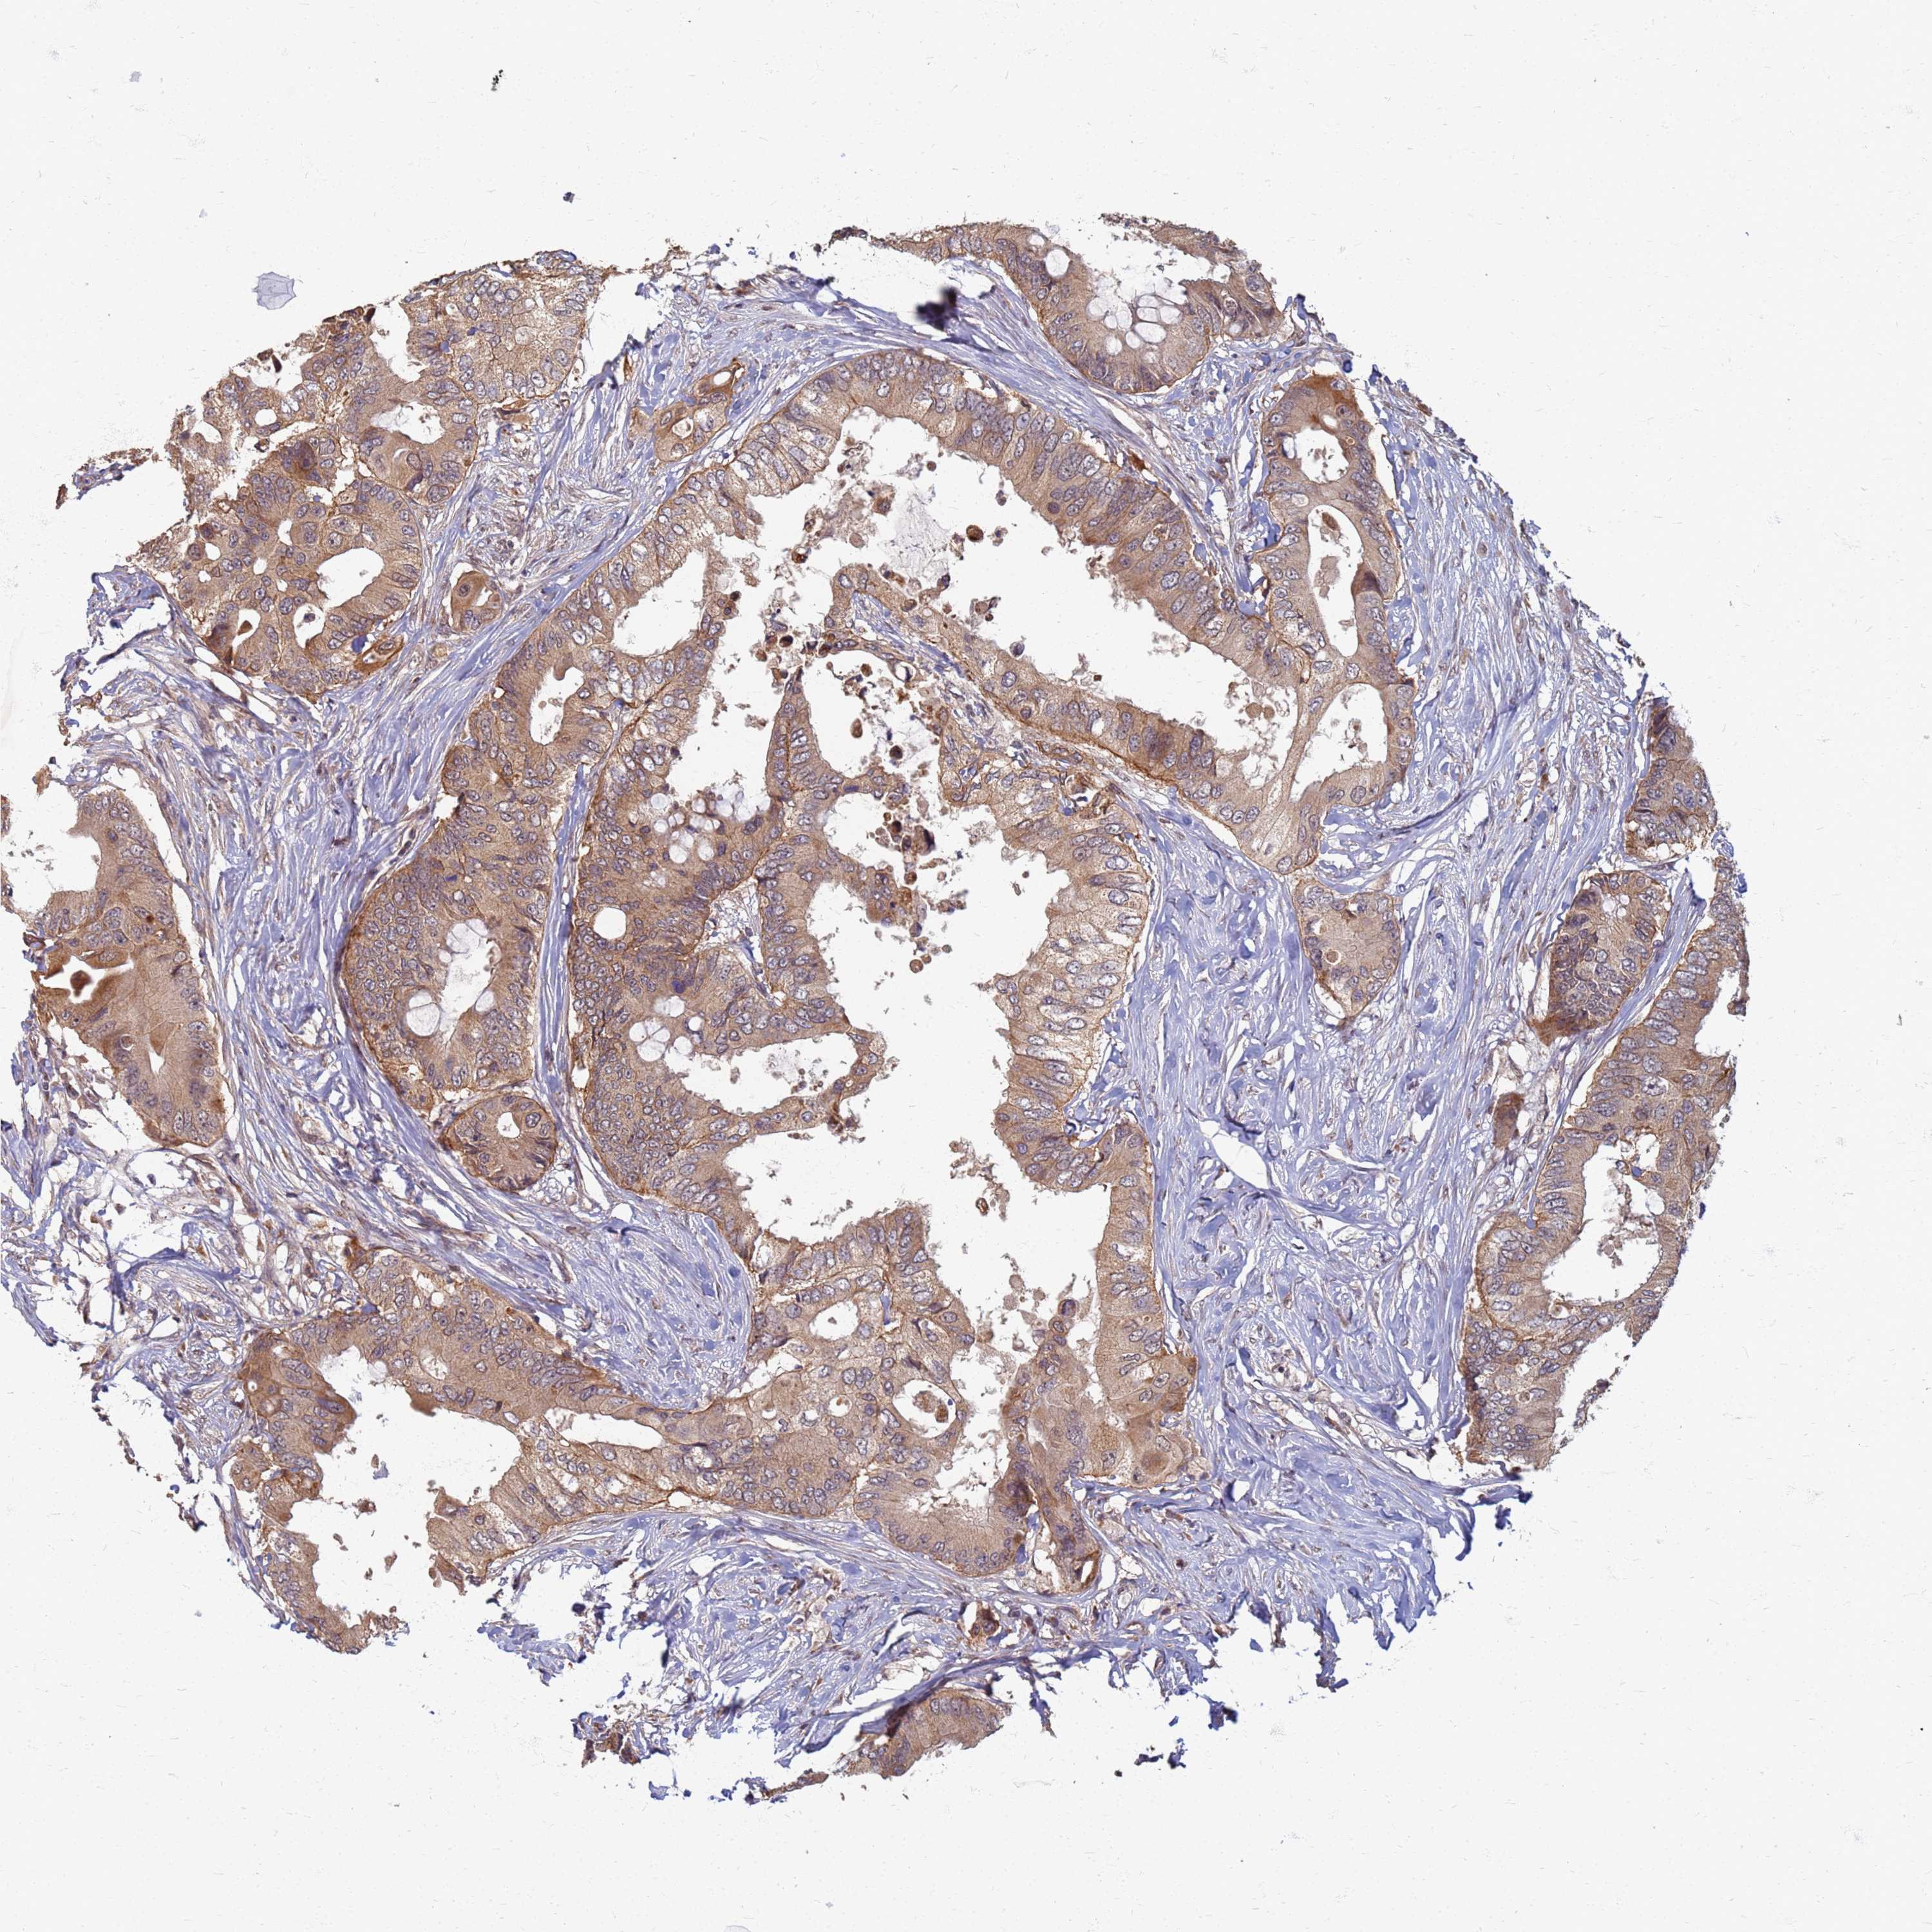

CANCER COLORECTAL CANCER Show tissue menu

Colorectal cancer

Human cancer

Colon adenocarcinoma